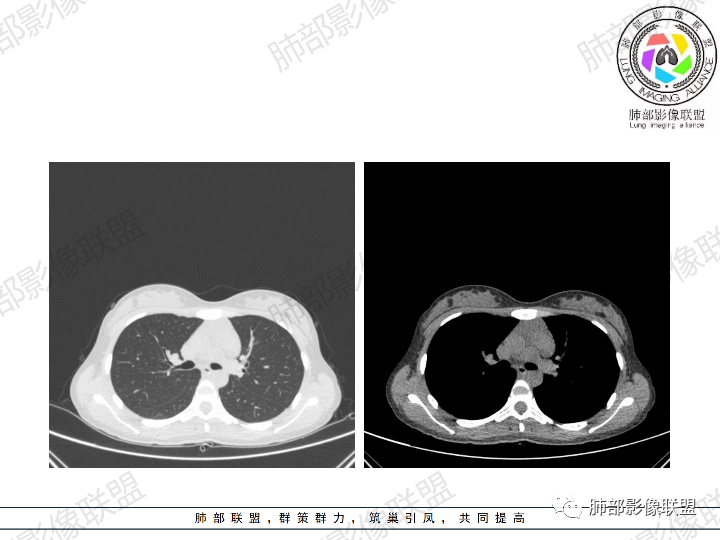

影像:前纵隔一实性肿块,形态不规则,沿主动脉间隙生长,部分包绕大血管,边界欠清,周围脂肪间隙消失,平扫密度尚均匀,增强扫描大部分强化不明显,病灶左下部分似有高强化,强化病灶与血管分界清楚,考虑:1淋巴瘤(一般居中,病灶较软,包绕血管)

女性,23岁,体检发现纵隔占位。CT示前纵隔不规则占位,沿间隙生长,局部包绕大血管及心包,增强内部可见部分区域呈明显渐进性强化,其余部分强化不明显,考虑囊性畸胎瘤或神经鞘瘤>淋巴瘤,太年轻不考虑胸腺瘤

青年女性患者,体检发现左前纵隔占位性病变,胸部CT:左前纵隔见一不规则占位性病变,整体边界清楚,紧贴血管,间隙不明显,内部密度尚均匀,未见钙化及脂肪密度,增强扫描不均匀轻度强化,总体考虑偏良性病变,胸腺增生?

这个病灶有点怪

1、形态,似乎与常规肿瘤不一致

2、有间隔

3、密度强化有点怪

这些边缘收缩

符合胸腺正常形态

这是腺体内的一个囊性病变:

这是腺体内的另一个

倾向于:一个正常增大的腺体内的病变

根据部位:腺体首先考虑胸腺,其次才考虑异位结构

胸腺内囊、实性占位

首先支持胸腺增生并感染

其次胸腺瘤

然后才考虑异位的病变

这个病例的特点就是病灶整体符合胸腺的形态,如果它是肿瘤,它周围侵袭性不明确的话,它应该膨隆的挺厉害,它单纯就是一个膨隆性生长的,那么它就应该是类圆形的,边缘应该是膨大的,但是这个病例不是,有些地方边缘是收缩的,那么就是原有的胸腺基础上内部出了问题,里面强化增生明显就有可能是在原有胸腺基础上里面滋生出来一个病变。年龄确实年轻,又是女性。胸腺里面的病例多是胸腺瘤、胸腺癌、淋巴瘤。既然定的是胸腺里面的病变,那么就在这里面考虑。淋巴瘤首先不是。那么就是胸腺瘤和胸腺增生,胸腺囊肿的说法也有很多,因为胸腺增生里面有一种就是囊性的增生,里面有些地方有强化,囊肿合并感染了可以有,慢性炎性的肉芽肿的可以有强化。不能排除胸腺瘤,胸腺瘤放后面,一个原因就是太年轻了。如果考虑胸腺瘤,年龄不太符合,心里不踏实。我认为大家不考虑胸腺瘤是正常的思维,写报告也是待排,放第一诊断不合适。考虑有胸腺瘤是因为强化,占位效应,间隔。